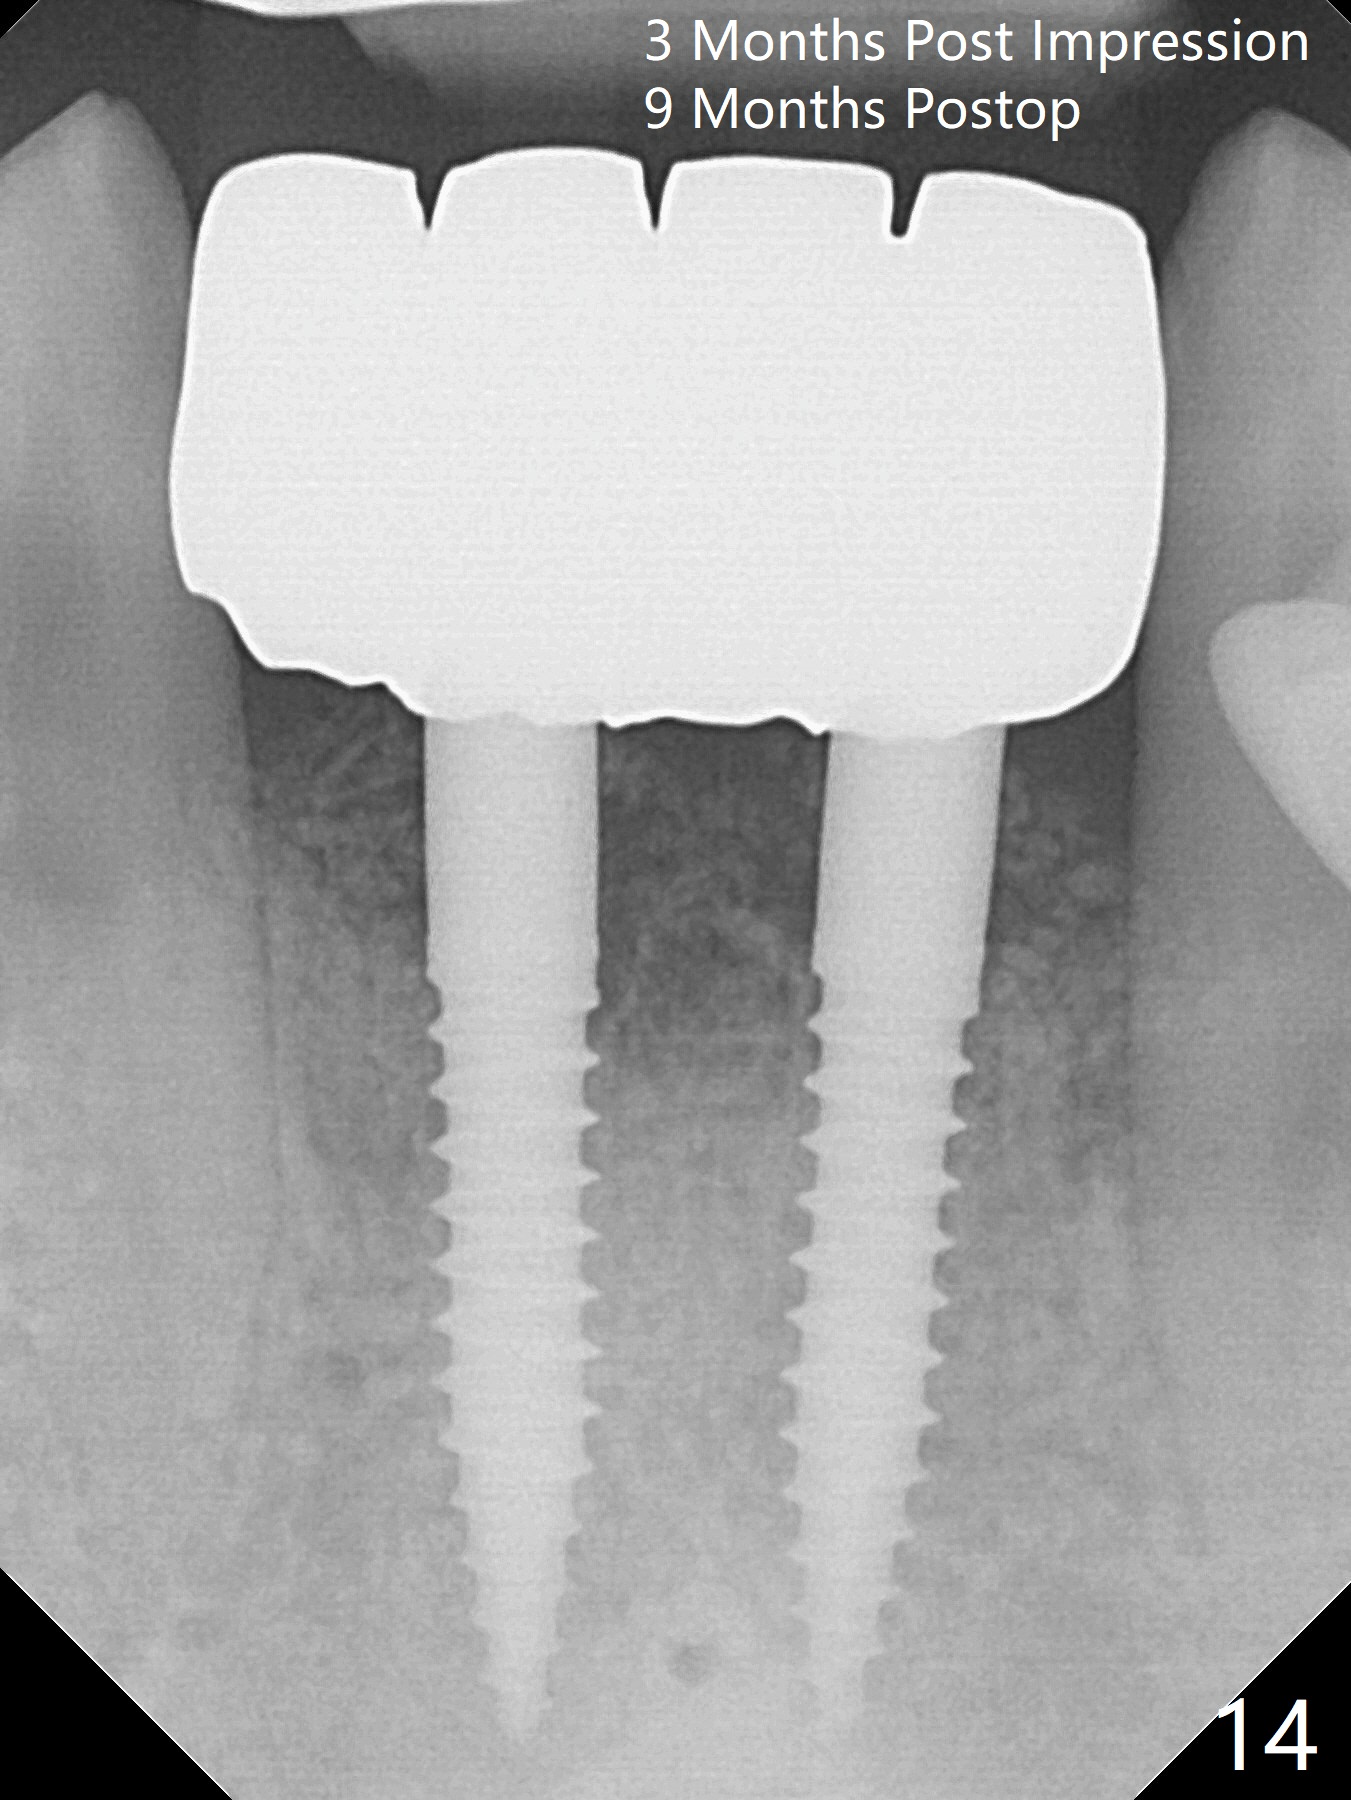

After extraction of 4 of the lower incisors, there are basically 2 sockets (#23/24 and 25/26), separated by the apparently midline bone (Fig.1 red line). In spite of using Lindamann bur to move the 25/26 osteotomy mesially, a 3x14(2) mm dummy implant remains close to the tooth #27 (Fig.2). The terminal branch of the Incisive Canal (<) is located between the lateral and central incisors. A de novo osteotomy (Fig.3 (1.5 mm drill)) is made mesial to the original one (O). While the 3x14(2) mm dummy implant is incompletely placed at #25/26, a 3x14(4) mm 1-piece one is placed at #23/24 (Fig.4). Finally the same implant is placed at #25/26 with placement of mineralized cortical/cancellous bone (Fig.5 *). When the large sockets are sutured, the supraerupted teeth #7-9 touch the lower gingiva (Fig.6). The incisal edge is reduced for clearance (Fig.7). Periodontal dressing is less likely to be dislodged with the incisal edge reduction (Fig.8,9). A provisional FPD is fabricated 1 week postop. Hard (Fig.10) and soft (Fig.11,12) tissues heal 5.5 months postop. The patient returns for crown cementation 3 months post impression (9 months postop, Fig.13,14).